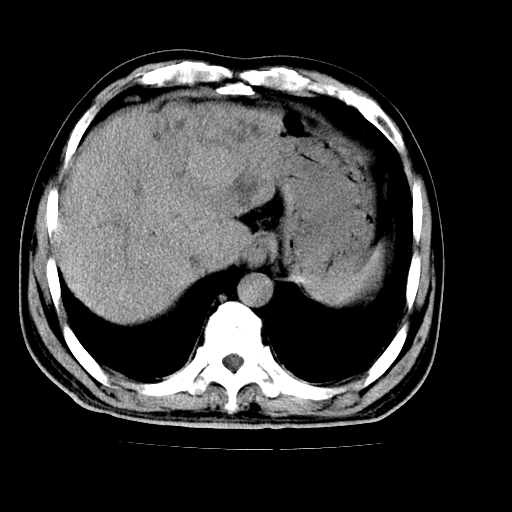

男,66岁,上腹部不适、黄染一周。彩超示:肝左叶占位,肝内胆管扩张,胆总管扩张,胆总管占位?

肝左叶不规则软组织肿块影,边缘不规整邻近肝实质受累分界不清;肝内胆管(左叶)明显扩张成“软藤状”,诊断:肝左叶胆管细胞癌。

肝左叶不规则软组织肿块影,边缘不规整邻近肝实质受累分界不清;肝内胆管(左叶)明显扩张成“软藤状”,诊断:肝左叶胆管细胞癌。胆囊钙乳症。

支持 1肝左叶肝内胆管细胞癌伴胆总管及门脉左支受侵。2胆囊钙乳症。

支持 1)肝左叶胆管细胞癌伴胆总管及门脉左支受侵。2)胆囊钙乳症。